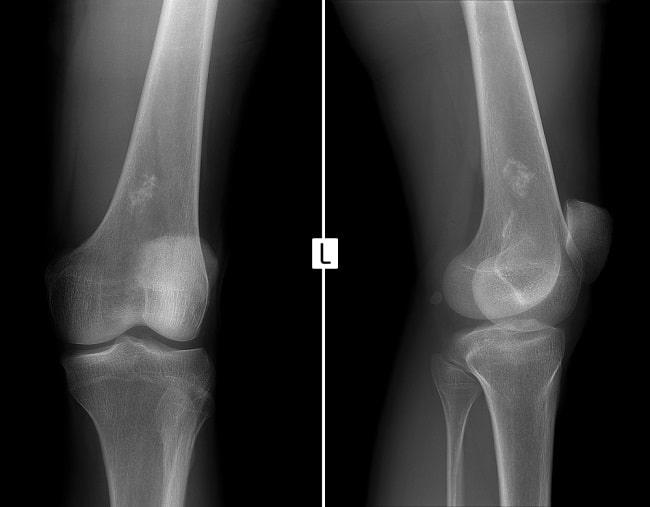

Pemeriksaan laboratorium dapat menunjukkan anemia dan leukositosis. Hasil pencitraan CT scan, MRI, dan rontgen akan memberikan gambaran onion peel pada pasien Ewing sarcoma.[1-3]